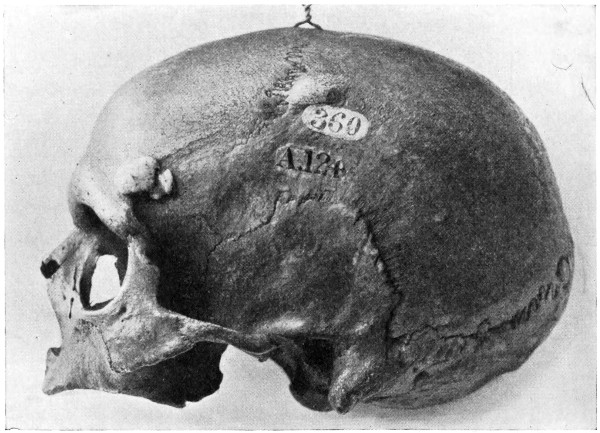

Fig. 20. An Occipital Cephalocele. (For further description, see text.)

1. Occipital cephaloceles—the commonest variety—occupy, anatomically, two positions (1) between the two lower segments of the occipital bone (inferior occipital cephaloceles), often involving the foramen magnum and sometimes complicated by a condition of cervical spina bifida, and (2) between the two upper segments of the occipital bone (superior occipital cephaloceles), occasionally involving the posterior fontanelle.

The tumour may possess a broad base or may be definitely pedunculated. In the former instance the gap in the bone may be of considerable size and the margins everted: in the latter case, the hole may be quite small.

The deformity is frequently associated with other congenital defects—hydrocephalus, microcephalus, spina bifida, hare lip, hernia, and talipes.

Sincipital cephaloceles are usually quite small, but the occipital variety and those situated in[35] the region of the anterior fontanelle frequently attain a great size (see Figs. 20-22).

Fig. 22. An Occipital Cephalocele. (For further description, see text.)